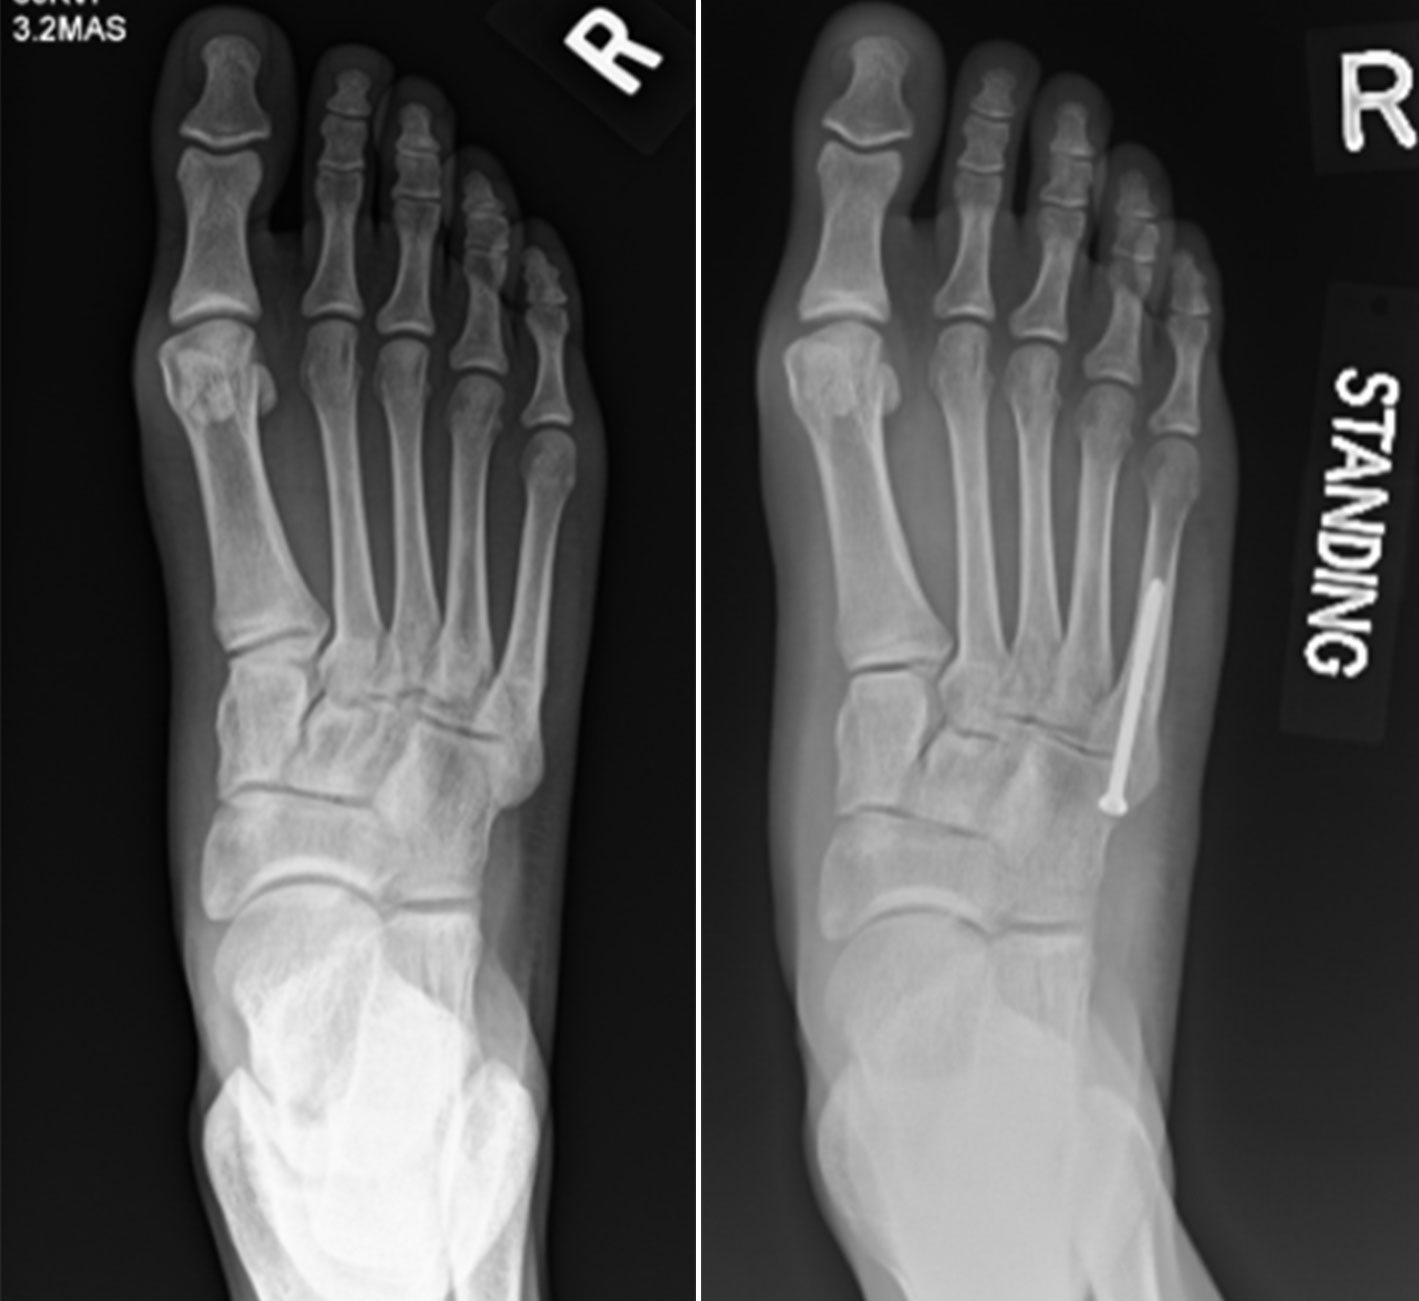

Jones fracture

(Left) X-ray shows a Jones fracture (stress fracture) at the base of the fifth metatarsal (arrow). (Right) An intramedullary screw has been used to hold the bone in place while it heals.